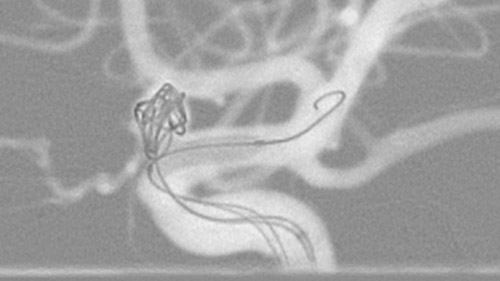

VasoCT visualizes small intra-cranial devices in vessel context with unmatched spatial resolution. Metal Artifact Reduction decreases streaking artifacts as from coil mass close to intra-cranial devices.